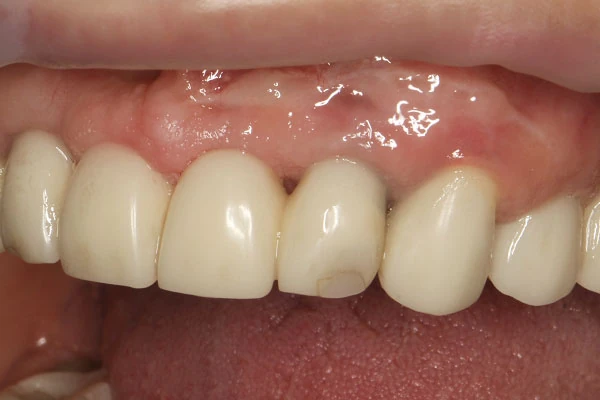

- недостаток мягких тканей при имплантации зуба

Создание прикрепленной десны в области 1-го имплантата7 600 ₽

Увеличение объема мягких тканей в области имплантата, создание зоны прикрепленной кератинизированной десны22 700 ₽